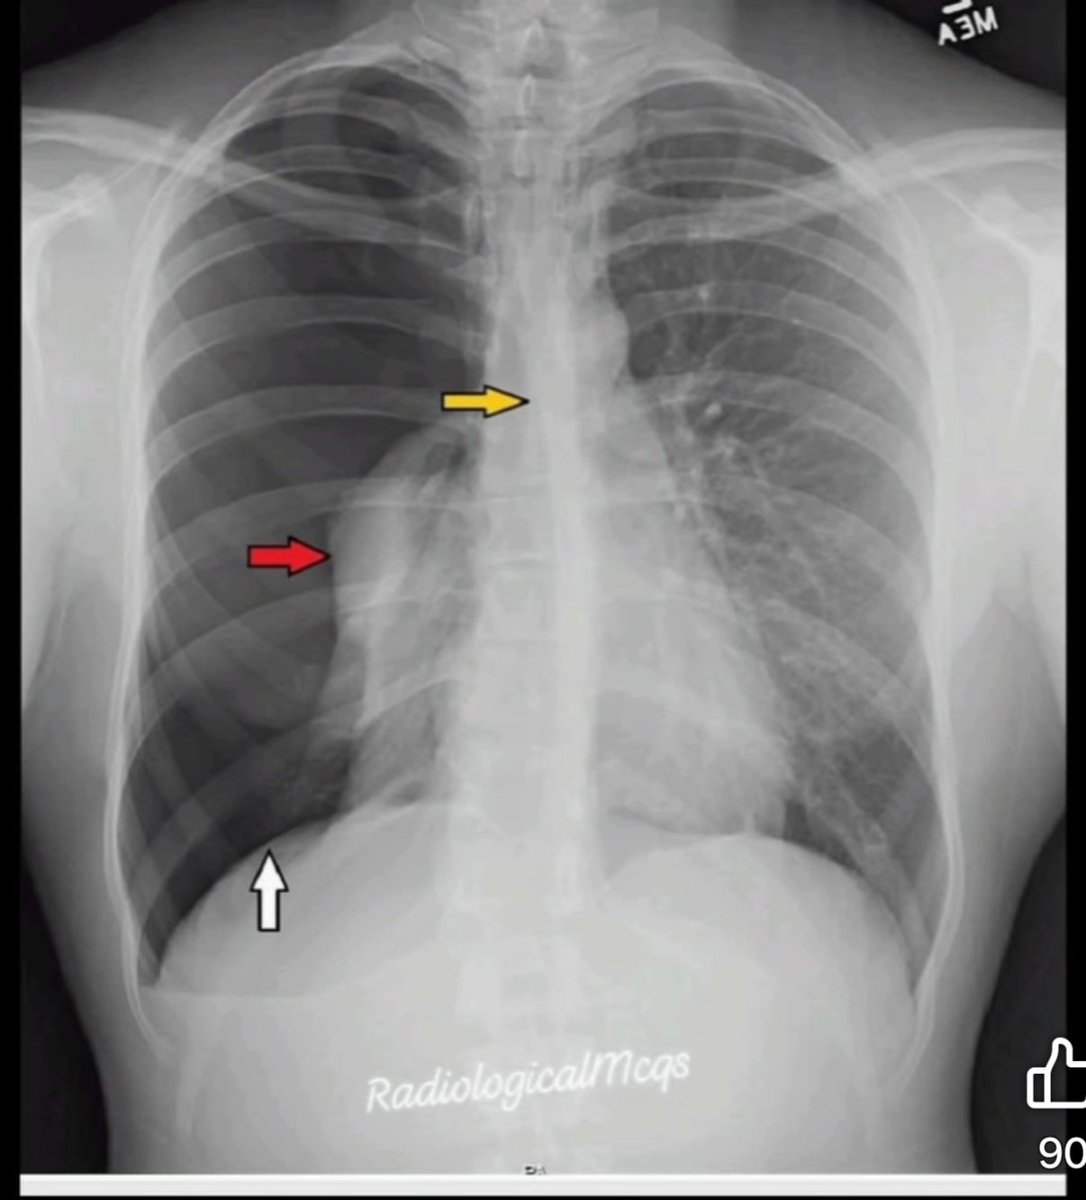

ABDOMINAL PAIN + DISTENTION + COFFEE BEAN SIGN. Choose the correct option A. Sigmoid volvolus B. Gastric Volvolus C. Midgut Volvolus D. I don’t know E. I don’t care #Xray

DrAyubaD's tweet image. ABDOMINAL PAIN + DISTENTION + COFFEE BEAN SIGN.

Choose the correct option

A. Sigmoid volvolus

B. Gastric Volvolus

C. Midgut Volvolus

D. I don’t know

E. I don’t care

#Xray